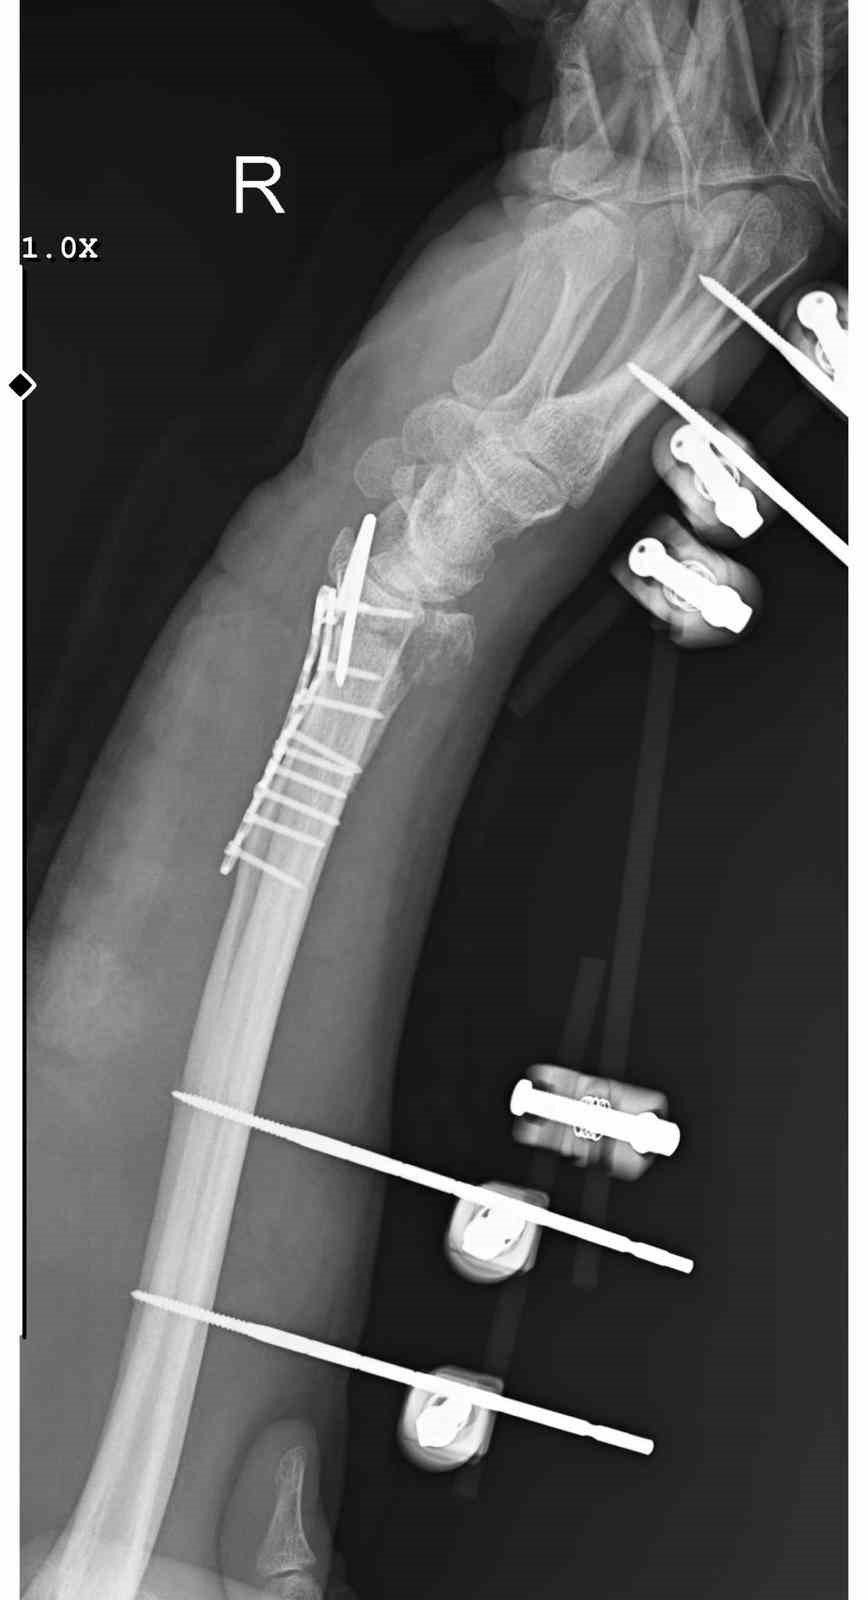

Ankara’nın Mamak ilçesinde, sahipsiz köpeklerden kaçarken ayağı kayarak düşen bir kişinin el bileği kırıldı. Ameliyatla 11 platin takılan şahsın kolunda kalıcı his ve hareket kaybı oluştuğu bildirildi.

Geçirdiği ameliyatın ardından konuşan Arslantaş, bileğinde ciddi hasar oluştuğunu belirterek,

“Bileğimde 15 dikiş ve 11 platin var. Yaklaşık 3 saat süren bir ameliyat geçirdim. Doktorlar, kalıcı his ve hareket kaybı olabileceğini söyledi” dedi.

Arslantaş, tedavi sürecinin aylarca süreceğini, uzun bir fizik tedavi döneminin kendisini beklediğini ifade etti.